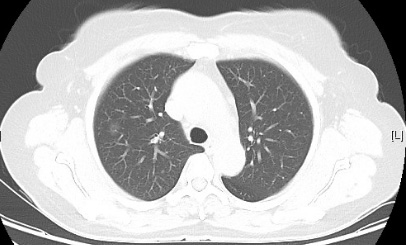

患者一因咳嗽、咳痰伴胸闷、喘憋半月余入院。胸部CT示左肺上叶升支2.8cm╳3.6cm肿块,有毛刺、分叶及胸膜牵拉。考虑为恶性肿瘤。常规支气管镜下并未发现异常,仅见到左肺上叶升支黏膜略充血水肿。

图1:胸部CT 图2:普通支气管镜下未见明显异常